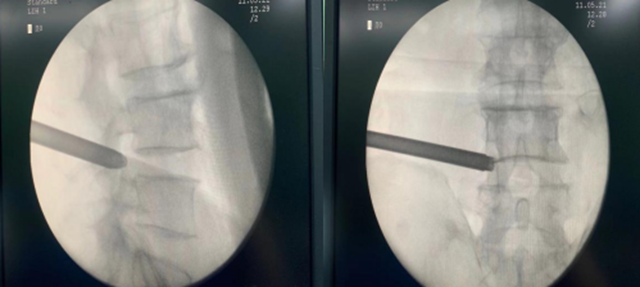

次日在刘庆教授团队的共同努力下,手术顺利完成。术中,韩聪医生从她腰椎取出10颗破碎的髓核。术后,刘嬢嬢很快觉得腰部、腿部一点也不疼了,第二天就能下床,前后不到一周就出院了。

手术创伤小,皮肤切口仅7mm,如同一个黄豆粒大小,出血不到10ml,术后仅缝1针,是同类手术中对患者创伤最小、效果最好的椎间盘突出微创疗法。